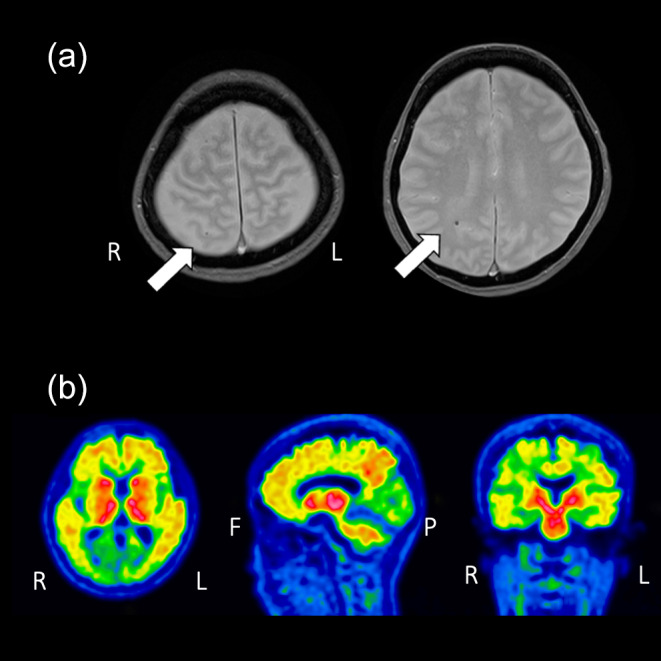

A case of severe ARIA with multiple infarctions and extensive microbleeds following lecanemab administration.